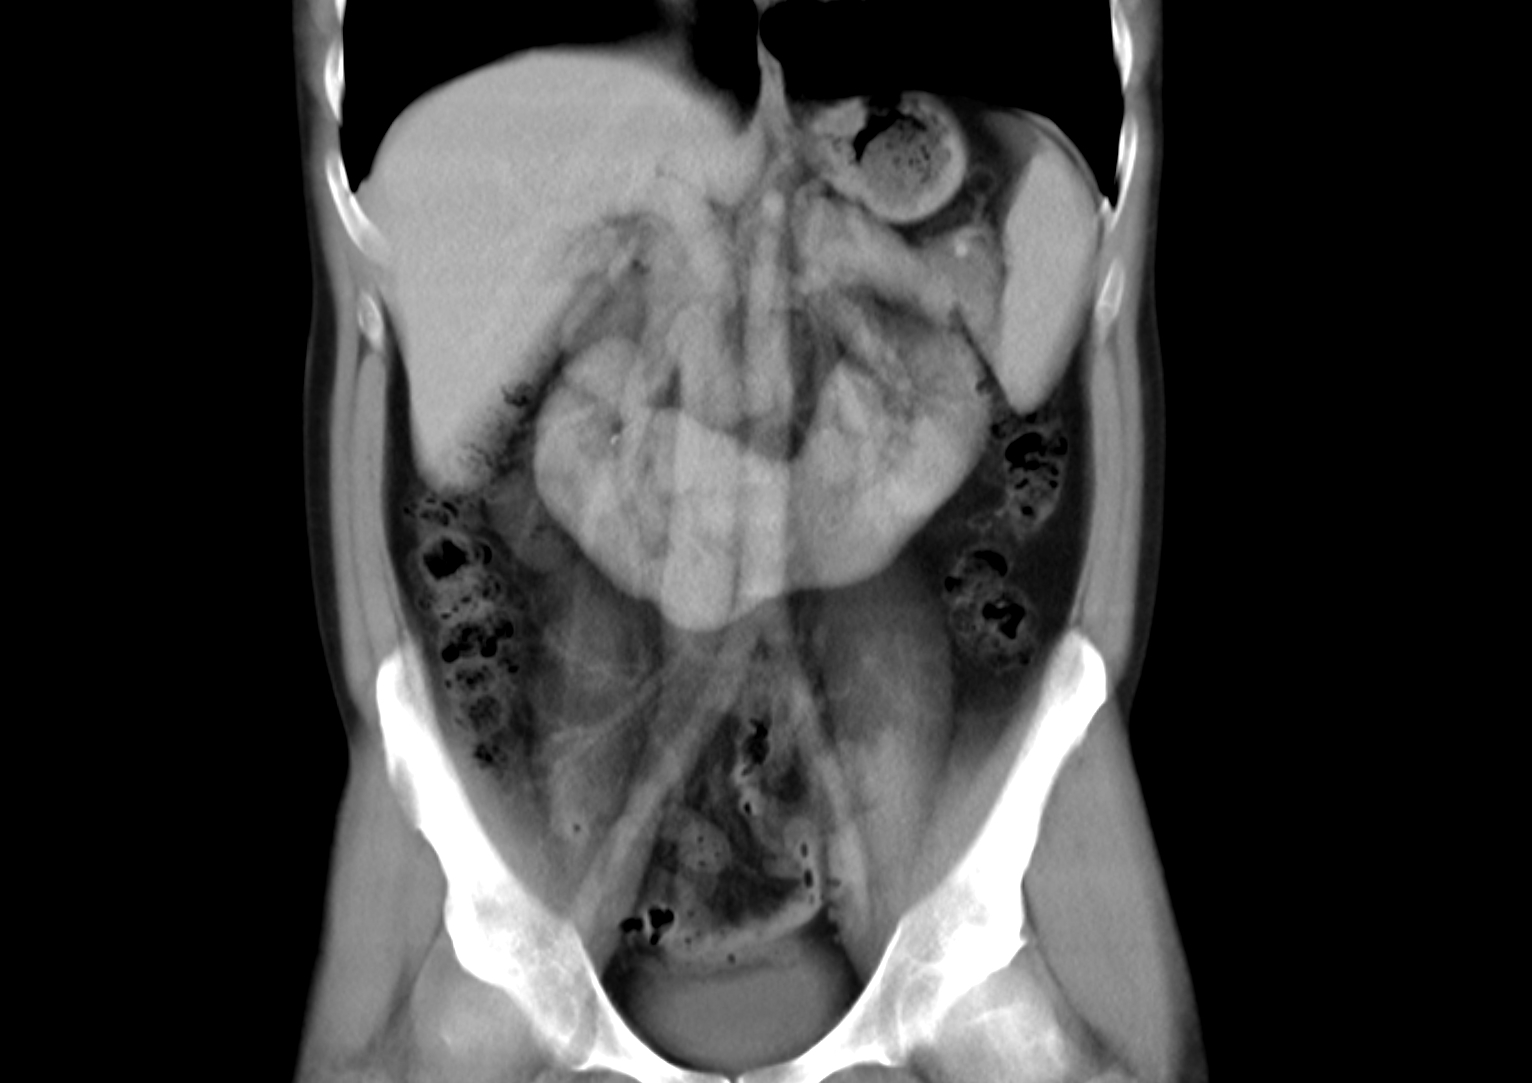

Horseshoe Kidney Rare . Horseshoe kidneys are the most common type of renal fusion anomaly. Get the facts on causes, treatments,. A horseshoe kidney is a congenital condition that causes the kidneys to join and form a horseshoe shape. Their location is abnormal as well. They render the kidneys susceptible to trauma and are an. Horseshoe kidneys are the most common fusion defect of the kidneys occurring in approximately 1:500 individuals. In 9 out of 10 cases, the kidneys fuse at the bottom, forming a “u”. As the name suggests, a horseshoe kidney is an abnormality where the two kidneys get fused together to form a horseshoe. If your child has horseshoe kidney, also called renal fusion, you’ve probably got a lot of questions. However, it's not just the shape and structure of the kidneys that is abnormal. Horseshoe kidney, or renal fusion, occurs when two individual kidneys fuse together as they rise from the lower belly.

Horseshoe kidneys are the most common type of renal fusion anomaly. Get the facts on causes, treatments,. In 9 out of 10 cases, the kidneys fuse at the bottom, forming a “u”. A horseshoe kidney is a congenital condition that causes the kidneys to join and form a horseshoe shape. Horseshoe kidney, or renal fusion, occurs when two individual kidneys fuse together as they rise from the lower belly. However, it's not just the shape and structure of the kidneys that is abnormal. Their location is abnormal as well. As the name suggests, a horseshoe kidney is an abnormality where the two kidneys get fused together to form a horseshoe. Horseshoe kidneys are the most common fusion defect of the kidneys occurring in approximately 1:500 individuals. If your child has horseshoe kidney, also called renal fusion, you’ve probably got a lot of questions.

Horseshoe Kidney Rare A horseshoe kidney is a congenital condition that causes the kidneys to join and form a horseshoe shape. In 9 out of 10 cases, the kidneys fuse at the bottom, forming a “u”. Horseshoe kidneys are the most common fusion defect of the kidneys occurring in approximately 1:500 individuals. However, it's not just the shape and structure of the kidneys that is abnormal. Their location is abnormal as well. Horseshoe kidney, or renal fusion, occurs when two individual kidneys fuse together as they rise from the lower belly. As the name suggests, a horseshoe kidney is an abnormality where the two kidneys get fused together to form a horseshoe. They render the kidneys susceptible to trauma and are an. Horseshoe kidneys are the most common type of renal fusion anomaly. If your child has horseshoe kidney, also called renal fusion, you’ve probably got a lot of questions. A horseshoe kidney is a congenital condition that causes the kidneys to join and form a horseshoe shape. Get the facts on causes, treatments,.